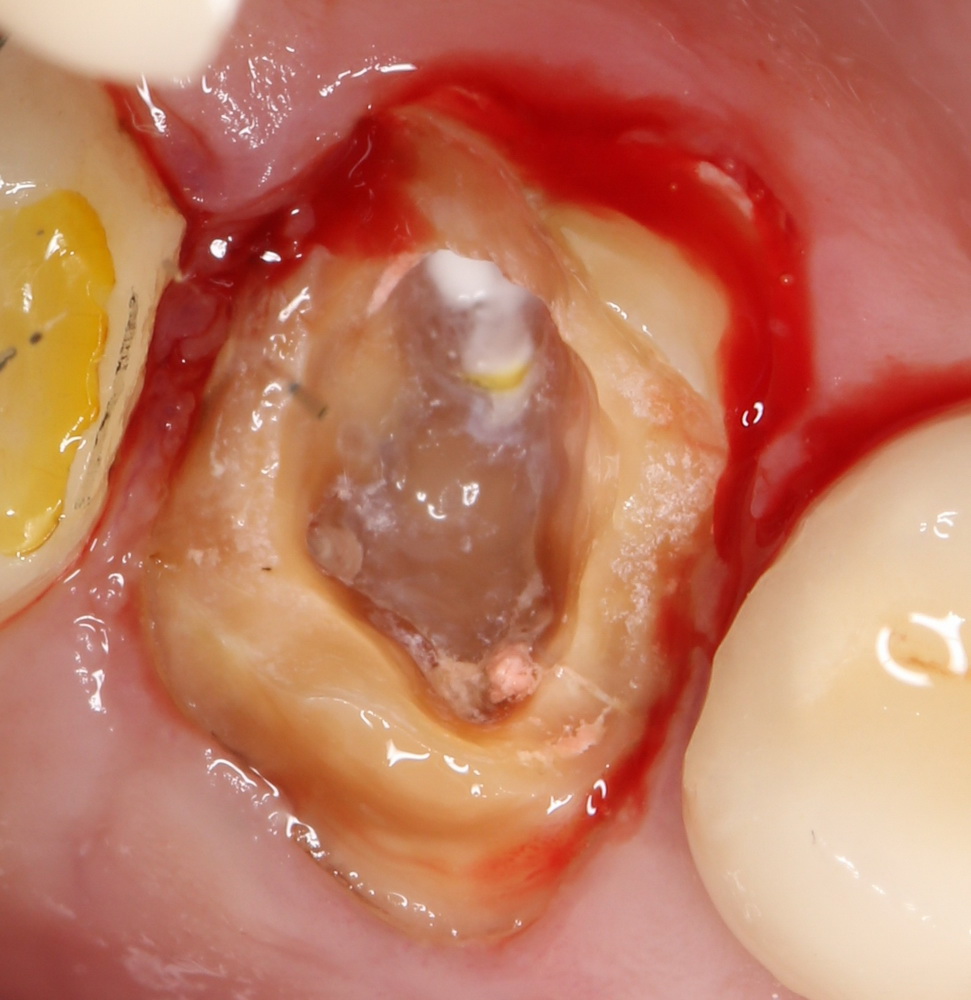

Герметичное ушивание операционной раны или лунок удаленных зубов

В этом состоит едва ли не главное отличие в хирургическом лечении пациентов на антиостеопорозной терапии. Если в нормальных условиях мы обычно оставляем лунки удаленных зубов открытыми «под кровяным сгустком» в надежде на заживление вторичным натяжением, то в случае с бисфосфонатами всё иначе. Инфицирование кровяного сгустка = инфицирование костных стенок лунки — стопроцентный остеонекроз.

Удаление зубов у пациентов, принимающих бисфосфонаты.

Во-первых, само удаление должно быть максимально аккуратным и щадящим. Как это сделать — читайте здесь>>, тут есть очень полезная и доступная статья.

Во-вторых, максимальное сохранение окружающей десны зуб — это наше всё. Если в процессе удаления разорвать десну на британский флаг, то, как нам подсказывает доктор Ясенхуй, о герметичном ушивании лунок можно забыть. Поэтому удаление зубов проводится методом фрагментации и с предварительным удалением коронковой части — так лучше видно десну и меньше шансов её повредить.

Нужно следить за тем, чтобы опилки от пломб, коронок и самих зубов не попали в лунки.

Далее — разрез. Он всегда более обширный, нежели при обычном удалении зубов, поскольку слизистую для ушивания лунки нужно мобилизовать. Намного удобнее проводить разрезы и формировать лоскуты до удаления корней зубов, сразу после «отпиливания» коронковых частей».

Корни зубов удаляются всё тем же методом фрагментации. Так, чтобы стенки лунки остались целыми. Как это сделать — написано тут>>.

После удаления корней зубов нужно резецировать и сгладить все острые края лунок, которые могут прорезаться в процессе заживления. И конечно же убрать все подвижные фрагменты кости, если таковые имеются.

Операция заканчивается ревизией лунок, заполнением их специальными препаратами и наложением швов. Операционная рана наглухо ушивается нерезорбируемым монофиламентным шовным материалом.